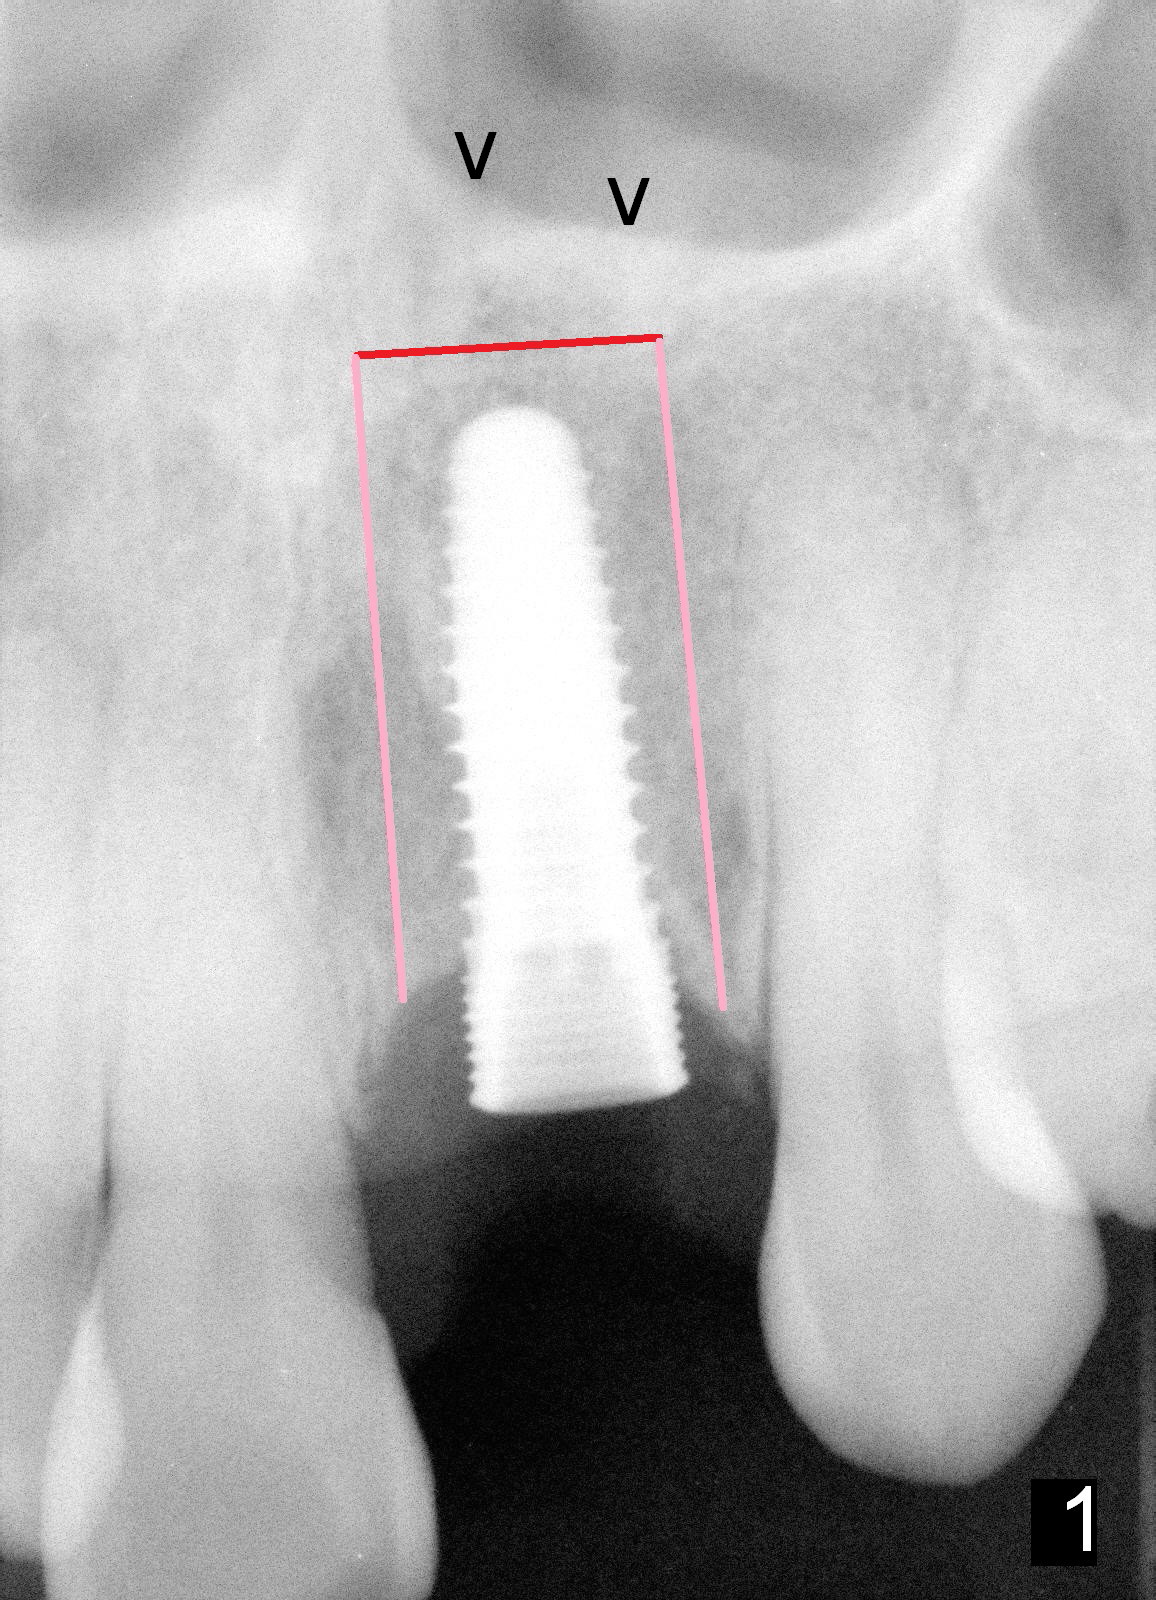

In contrast, delayed implant is most likely associated with mal-positioning in 3 D, including invasion of the nasal floor (Fig.3) due to bone loss. When segemental osteotomy is needed, the transverse cut is difficult (Fig.4). The implant bone segment may be not stable once moved (Fig.5), since no block graft can be inserted, not to mention trauma and hemorrhage in the nasal floor. The segment may relapse (Fig.6).